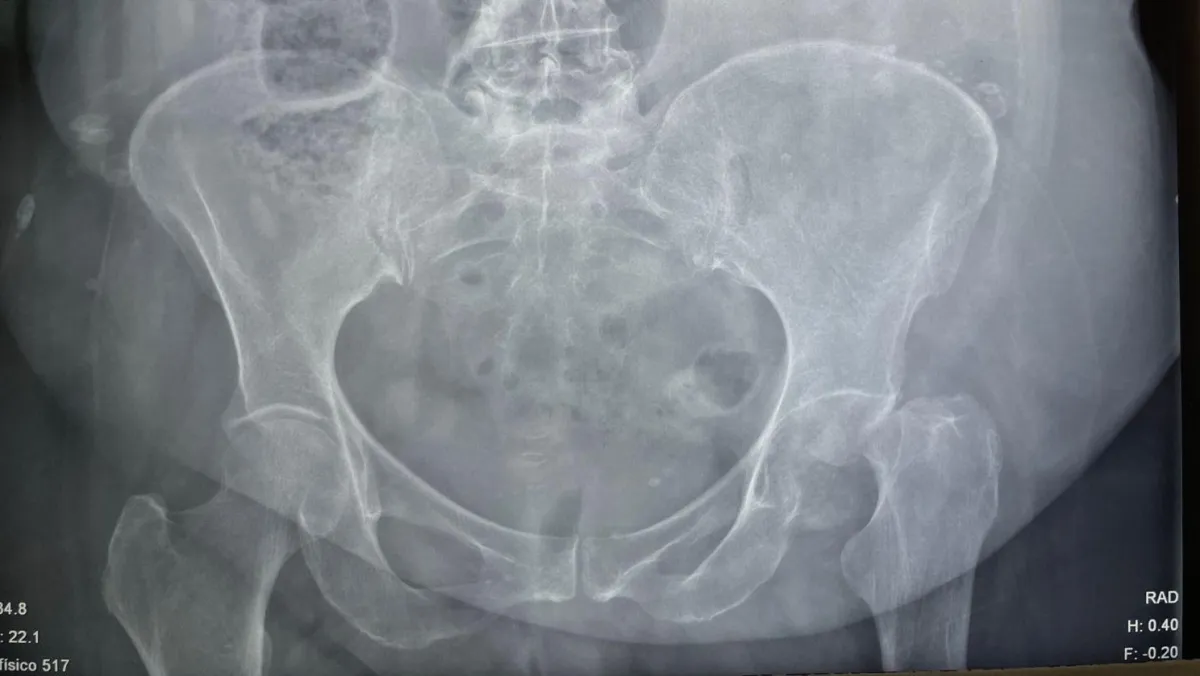

Paciente de 99 años

Fractura de cadera tratada con clavo TFNA

Paciente de 99 años con fractura de cadera. Se realizó fijación con clavo TFNA. Cada caso se evalúa de forma individual.